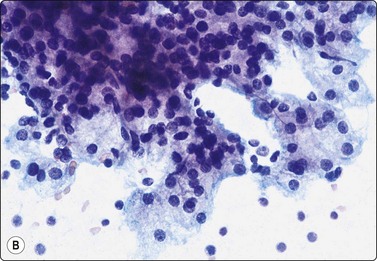

image image

Fig. 4.9 Nasopharyngeal carcinoma (undifferentiated, lymphoepithelial type, WHO type III)

Loose clusters of undifferentiated epithelial cells with vesicular nuclei, prominent nucleoli and pale fragile cytoplasm. Background of lymphocytes. (A, MGG, HP; B, H&E, HP).

Nasopharyngeal carcinoma (NPC) is a clinicopathologic entity different from other squamous cell carcinomata of the head and neck. It is distinguished by its particular histology, geographic distribution, relationship to Epstein-Barr virus, and the absence of an alcohol or tobacco etiological relationship. A proportion of NPCs show squamous differentiation and the cytological pattern of non-keratinizing squamous cell carcinoma (squamous cell carcinoma/WHO type II) (Fig. 4.8). Keratinized cells (WHO type I) are uncommonly found. The majority of NPC are poorly differentiated or undifferentiated. Cells from undifferentiated NPC (UCNT, WHO type III) form loose clusters with no specific microarchitectural pattern, and are usually mixed with lymphoid cells. In the ‘lymphoepitheliomatous’ type (Schmincke-Regaud) the cells tend to be less cohesive, resembling Hodgkin’s disease or large cell non-Hodgkin lymphoma. However, in NPC, the malignant cells are still clustered and have more abundant pale cytoplasm contrasting with the lymphoid cells in the background (Fig. 4.9). Plasma cells are frequently found among the lymphoid cells. Immunostaining for cytokeratin and a pan-lymphocyte marker is helpful. Epstein-Barr virus-associated nuclear antigen is demonstrable by anticomplement immunofluorescence in undifferentiated tumors. Other patterns of growth may occur and may cause diagnostic problems; for example, spindle cell forms may be difficult to recognize as carcinoma.

NPC frequently presents to the cytologist as a lymph node metastasis in the neck without a known primary. Cytological recognition is important since the primary is often clinically occult.